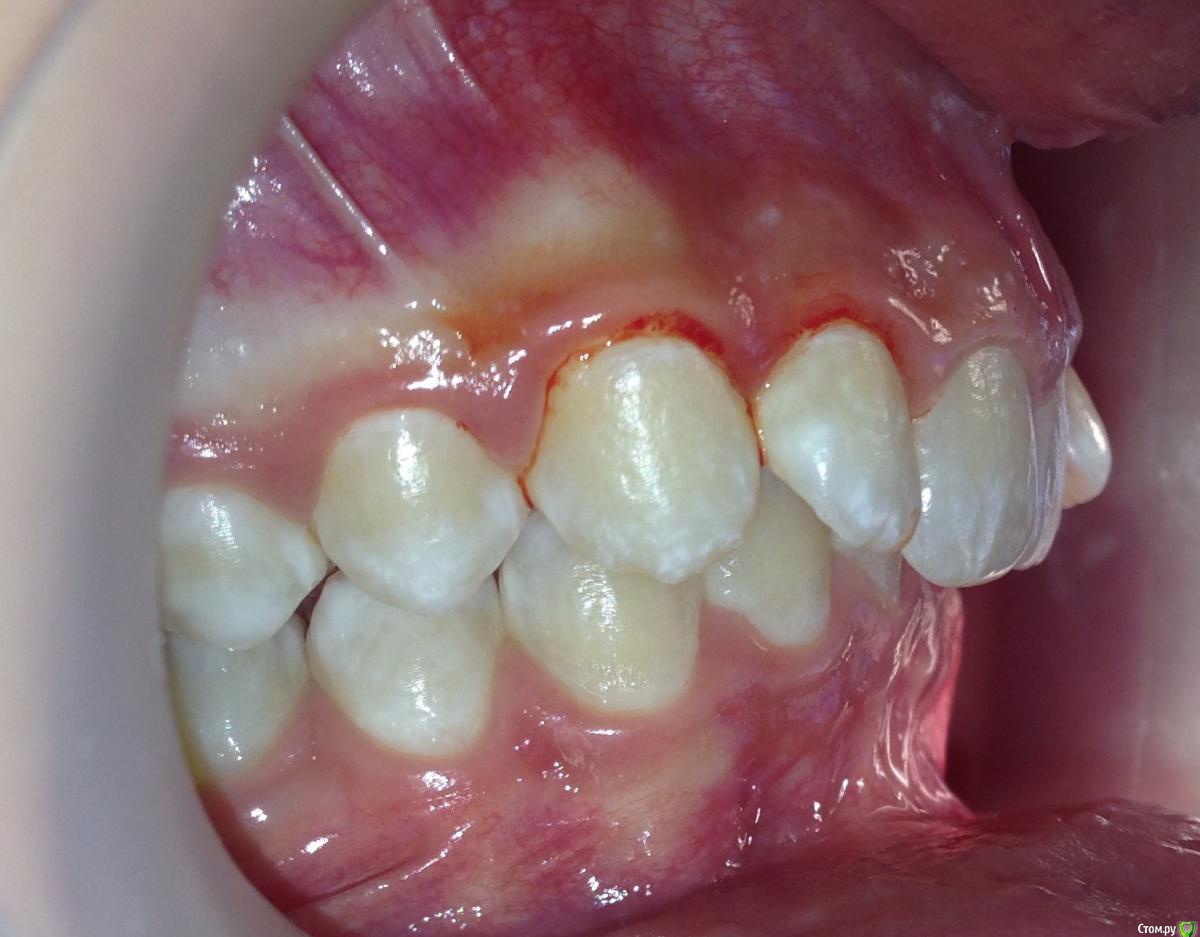

Пациентка 14 лет. Было принято решение лечить без удаления, тк. профиль не позволяет да и ретропозиция нч. Лечение идет. Я назначила ранние эластики слабые, на 17/25 нити на вч и 18 нити на нч. по 2 классу короткие 3,4-4,5. Пациентка пришла через месяц жалуется на щелканье челюсти во время ношения эластиков и сразу после их снятия. Т.е. если открывает рот, то челюсть скачкообразно двигается и щелчками. Последние 2 недели, когда много говорит, то вообще стала заедать. Это она так сказала. После отмены эластиков (страшно), через неделю пришла, рот открывает ровно, без девиации, щелчков нет. Вопрос: почему щелкает и что с этим делать? По поводу прикуса, посоветуйте, пожалуйста, как нормализовать? Аппарат типа гербста? может ей твинблок сделать? Эластики? К сожалению другими методами я пока что не владею. Спасибо, очень жду ваших советов.

Конечно, через интеонет трудно ответить, ведь щелчки бывают разные (в начале фазы открывания, в конце, в начале фазы закрывания, в конце закрывания? То есть если у нее смещена головка кзади ппи щакрытом рте, то при открывании у нее сразу должен быть щелчок (головка догнала диск), пожевала .., потом во время закрытия в самом конце опять щелчок (головка съехала с диска и стала в свое привычное положение). Это обычная картина при втором классе. Несьемные аппараты не будут давать уходить челюсти назад, щелчков быть не должно. После снятия аппарата зафиксируете новое положение челюсти бугорками антагонистов